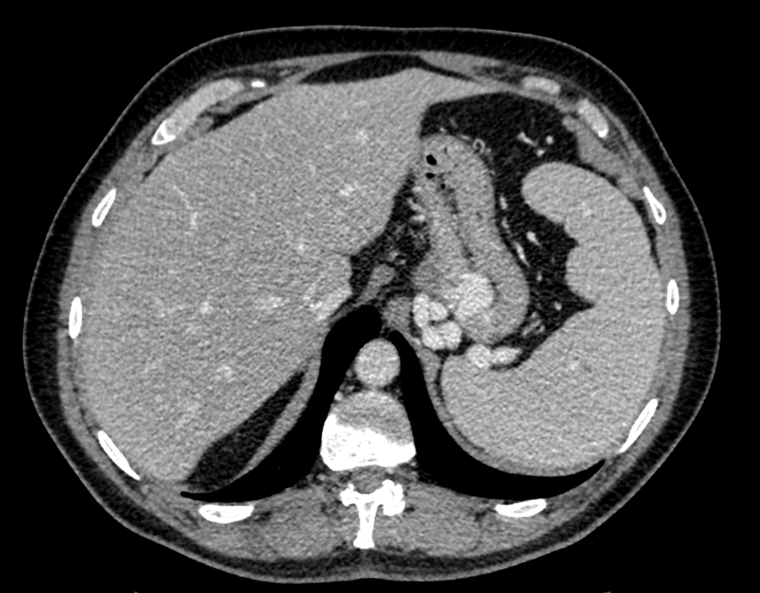

Signs of portal hypertension

Presence of enlarged portosystemic collateral vessels in the chest and upper abdomen. Coronary venous collaterals are typically associated with esophageal or paraesophageal varices. Esophageal varices are commonly fed by the anterior branch of the left gastric vein, while the posterior branch of this vein supplies paraesophageal varices. On CT, varices are distinct, round, tubular, or winding structures that exhibit smooth, homogeneous attenuation and enhance with contrast material to a similar degree as neighboring portal and mesenteric veins.